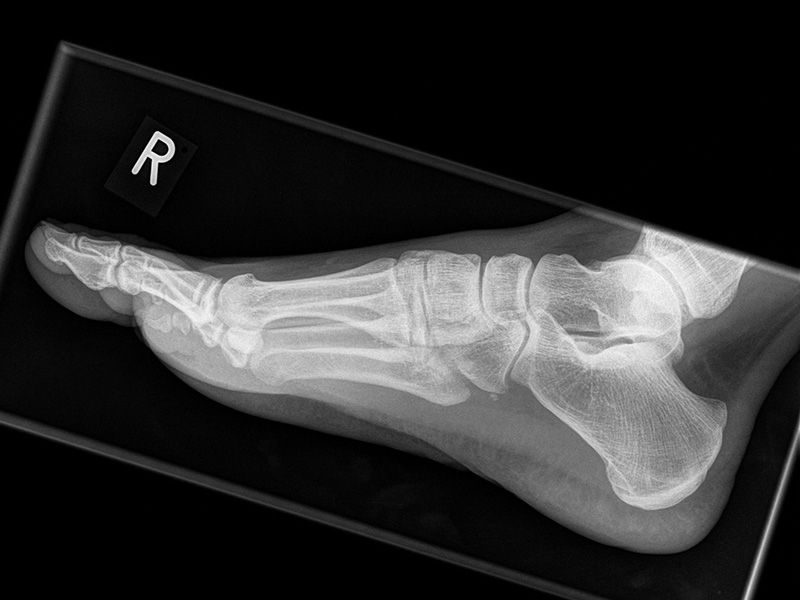

Fuß seitlich mit Belastung

Positionierung:

• Der Patient steht auf beiden Füßen mit gleichmäßiger Lastverteilung.

• Der zur Röntgen der Fuß wird längs des Films positioniert.

• Die Kassette steht senkrecht zum Boden, medial dem Fuß anliegend.

• Der Zentralstrahl wird von lateral nach medial zentriert auf das Kalkaneokuboidalgelenk knapp cranial der Os metatarsale V Basis ausgerichtet.

• Die Röntgenröhre steht 0° horizontal.

Kennzeichen des Röntgenbildes:

• Standardabbildung des Fußes zusammen mit der belasteten d.-p. Aufnahme und der unbelasteten 45° Pronationsaufnahme.

• Überblick über die Fußanatomie und Fußstatik.

• Die seitliche Aufnahme liefert Informationen zur Stabilität des Längsgewölbe und zu den Achsen von Talus, Kalkaneus und Metatarsale I.

• Die Aufnahme wird eingesetzt zur Darstellung von freien Gelenkkörpern sowie knöchernen Veränderungen am Achillessehnenansatz oder der Plantarfaszie.

Besondere Bemerkungen zum Beispielbild:

• Schwere Hallux valgus Deformität.

• Die Sesambeine sind luxiert, ebenso das Großzehengrundgelenk. Luxation des Metatarsophalangealgelenks II.

• Degenerative Veränderungen der tarsometatarsalen (TMT) Gelenkreihe, betont TMT II und III.

Zur Vollansicht und zum Lesen der Bildbeschreibung bitte die Bilder anklicken.